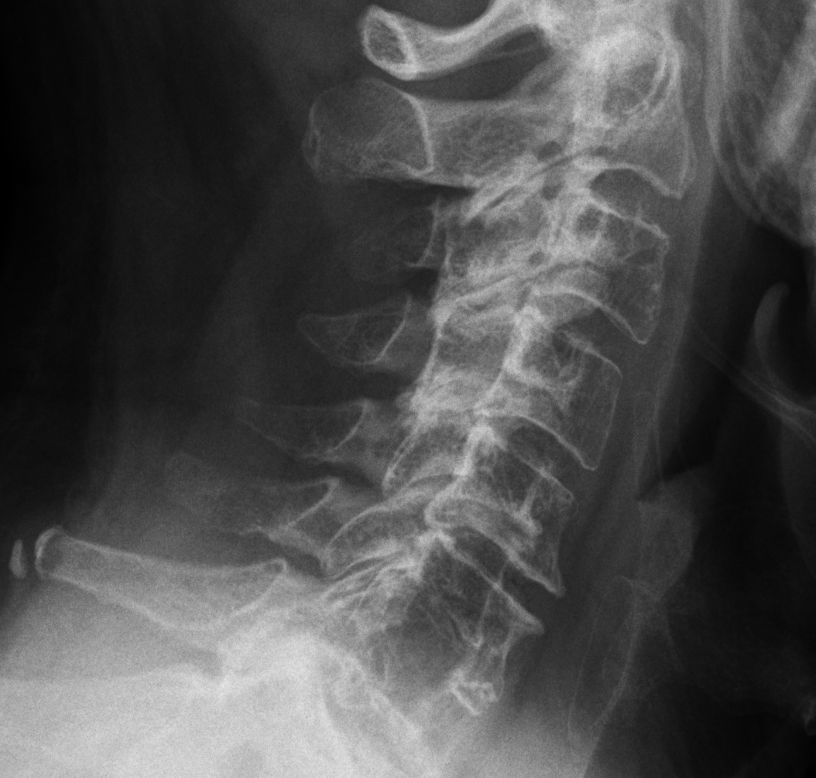

63-jähriger Mann mit multiplem Myelom Stadium IIIA.

Stabilitätsgefährdende Lysre in 6 und 7.![]() | |